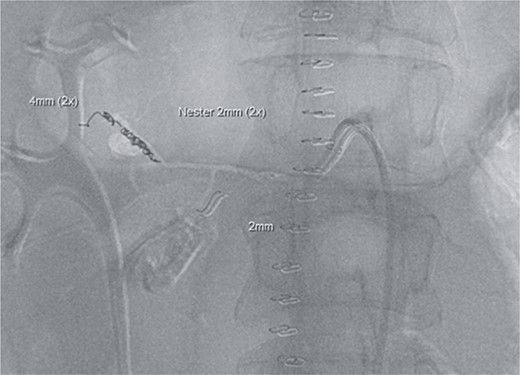

However, on the 16th day following the initial surgery, there was another active bleeding from the pancreaticoduodenal artery, distal to the previously placed coil. This bleeding was also managed interventionally (Figs 4 and 5).

Angiography showing another aneurysm with active bleeding, proximally to the previously coiled site.

Postinterventional angiography, after interventional bleeding control, using coiling.